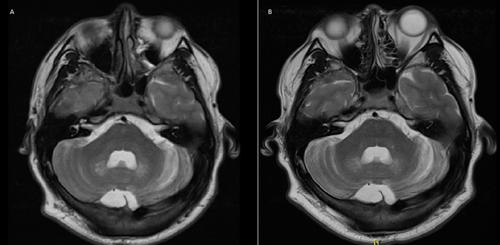

Cerebrotendinous xanthomatosis (CTX) is an inherited metabolic disease due to biallelic pathogenic variants in CYP27A1. We report a newly diagnosed patient and the outcome of the chenodeoxycholic acid (CDCA) treatment. This is a 36-year-old male with progressive lower limb spasticity, learning difficulties, and early cataracts. He was diagnosed by targeted next generation sequencing panel for hereditary spastic paraparesis (c.379C>T; p.Arg127Trp and c.1072C>T; p.Gln358* in CYP27A1) with CTX at the age of 33 years. Brain and spine magnetic resonance imaging (MRI) revealed increased T2 signal intensity in the dentate nuclei and bilateral posterolateral spinal cord. Baseline plasma 7a-hydroxy-4-cholesten-3-one (> 5; ref. range < 0.300 nmol/mL) and 7a,12a dihydroxycholest-4-en-3-one (> 5; ref. range < 0.100 nmol/mL) were markedly elevated. Baseline full-scale IQ was 69. The CDCA treatment (750 mg/day) was started at the age of 34 years. Plasma 7a-hydroxy-4-cholesten-3-one level was normalized; plasma 7a,12a dihydroxycholest-4-en-3-one level was markedly improved (0.755 nmol/mL; ref. range < 0.1) and full-scale IQ improved to 83 at two years of the CDCA treatment. This patient highlights improvements in neurocognitive functions despite late diagnosis and late initiation of treatment and exemplifies the importance of diagnosing a treatable disease at any age to improve neurocognitive outcomes.